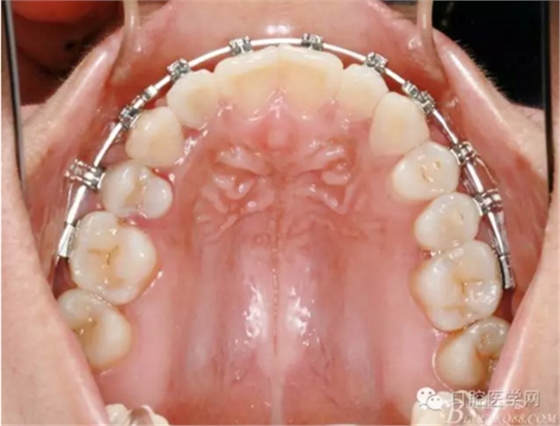

正畸醫(yī)生都想把患者做到“理想頜”,而臨床工作中卻很難如愿;這個(gè)患者到診時(shí),口內(nèi)已經(jīng)有兩顆恒牙缺失;

37,45缺失后,鄰牙近中移動(dòng)占據(jù)了部分牙位;患者要求減少治療費(fèi)用,不做種植修復(fù),那怎么協(xié)調(diào)右側(cè)的咬合關(guān)系?

15是根管治療過的牙齒,只好忍痛舍去......

在滿足功能的前提下,退而求其次...有時(shí)候,正畸醫(yī)生不得不妥協(xié)。